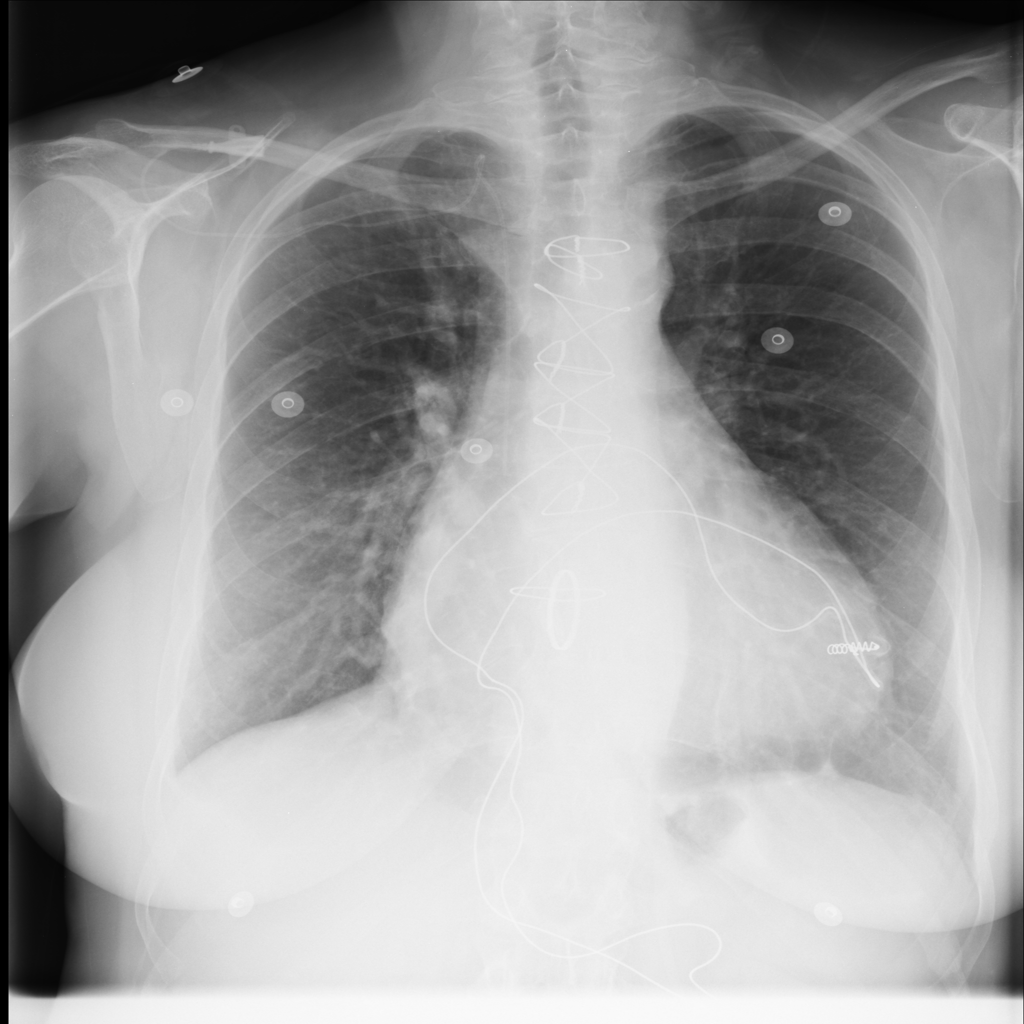

PAT-3384 · IMG-000Cardiomegaly

PAT-3384 · IMG-000

AP